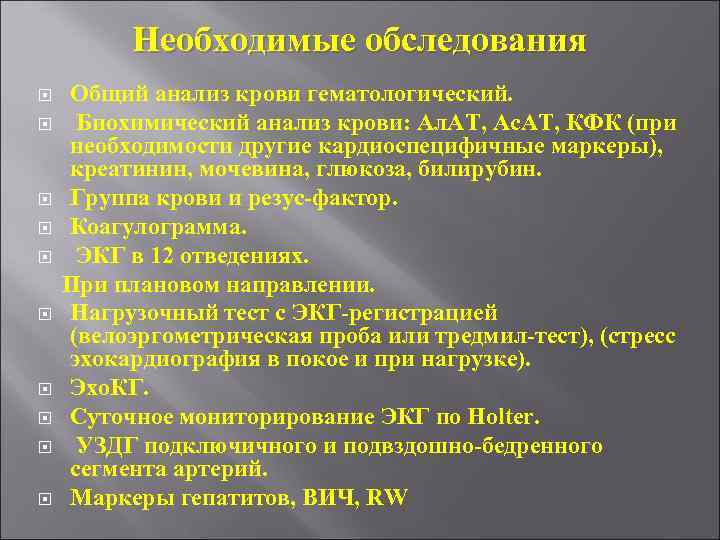

Необходимые обследования Общий анализ крови гематологический. Биохимический анализ крови: Ал. АТ, Ас. АТ, КФК (при необходимости другие кардиоспецифичные маркеры), креатинин, мочевина, глюкоза, билирубин. Группа крови и резус-фактор. Коагулограмма. ЭКГ в 12 отведениях. При плановом направлении. Нагрузочный тест с ЭКГ-регистрацией (велоэргометрическая проба или тредмил-тест), (стресс эхокардиография в покое и при нагрузке). Эхо. КГ. Суточное мониторирование ЭКГ по Holter. УЗДГ подключичного и подвздошно-бедренного сегмента артерий. Маркеры гепатитов, ВИЧ, RW

Необходимые обследования Общий анализ крови гематологический. Биохимический анализ крови: Ал. АТ, Ас. АТ, КФК (при необходимости другие кардиоспецифичные маркеры), креатинин, мочевина, глюкоза, билирубин. Группа крови и резус-фактор. Коагулограмма. ЭКГ в 12 отведениях. При плановом направлении. Нагрузочный тест с ЭКГ-регистрацией (велоэргометрическая проба или тредмил-тест), (стресс эхокардиография в покое и при нагрузке). Эхо. КГ. Суточное мониторирование ЭКГ по Holter. УЗДГ подключичного и подвздошно-бедренного сегмента артерий. Маркеры гепатитов, ВИЧ, RW